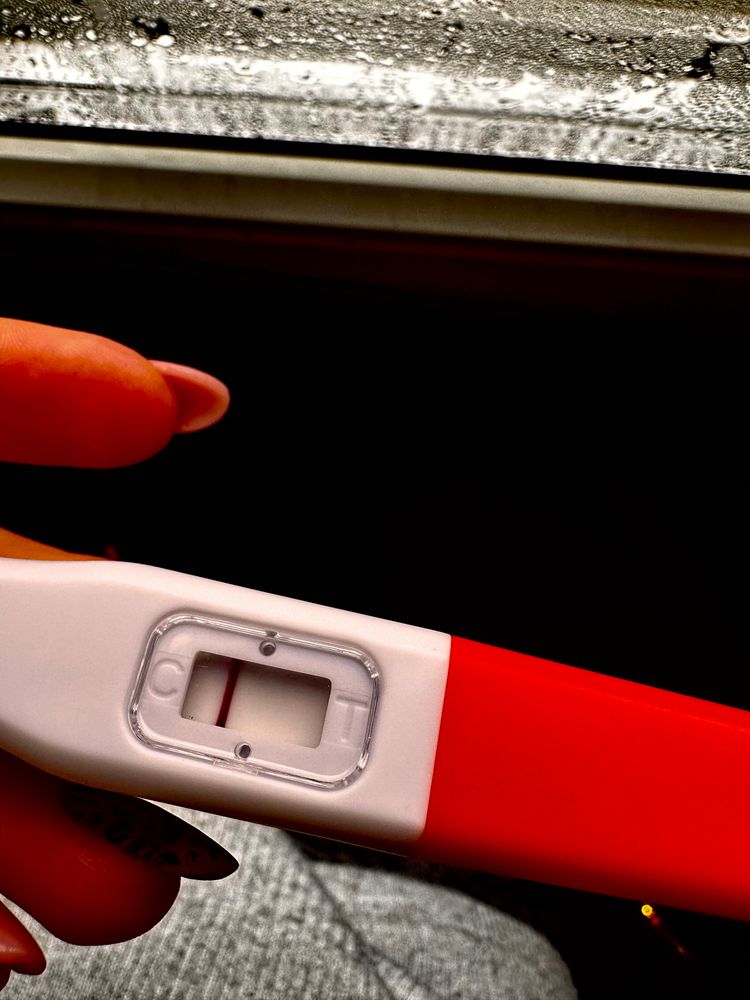

у меня в беременность именно тесты на овуляцию показали жирные // , сделала тест на б и была еле заметная полоска . Сейчас прикреплю . Но к сожалению замерла на 6 Нед

Ответить

Алина Горева, сочувствую😔

а тесты на овуляцию уменьшались после овуляции? Или тоже оставались насыщенными?

Ответить

Мама двоих (4 года, 1 год)

Алина Горева, прям сразу после овуляции? Такие жирные как у меня после 01.02? Или жирнее?)